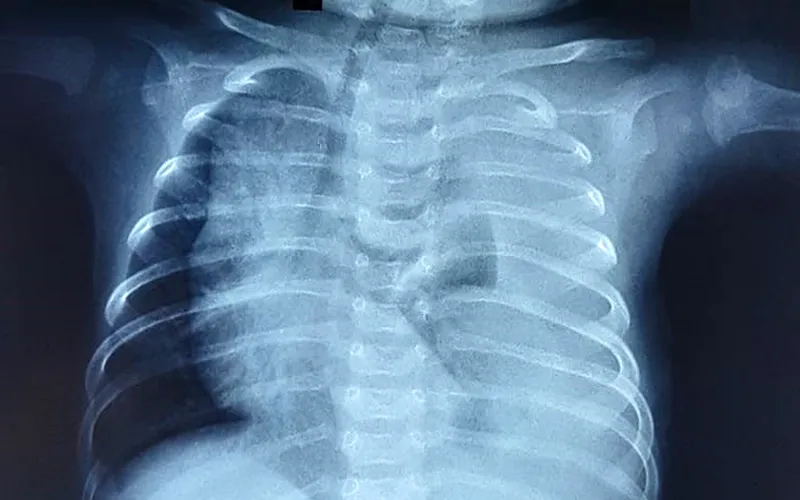

2.8. X-quang phổi

• Vai trò:

• X-quang phổi là một công cụ hữu ích trong việc phân biệt giữa các rối loạn tim và phổi. Việc kiểm tra các trường phổi giúp xác định các nguyên nhân phổi chính gây tím tái, bao gồm tràn khí màng phổi, giảm sản phổi, thoát vị cơ hoành, phù phổi, tràn dịch màng phổi hoặc bệnh đường thở.* Các đặc điểm gợi ý tổn thương tim:

• Ba đặc điểm của phim X-quang ngực có thể gợi ý các tổn thương tim cụ thể là kích thước hoặc hình dạng tim, dấu hiệu mạch máu phổi và vị trí của cung động mạch chủ. * Kích thước hoặc hình dạng trái tim: * Kích thước tim: Bệnh nhân có tổn thương tắc nghẽn bên trái có thể bị tim to do suy tim. Tim cực to gợi ý các tổn thương liên quan đến tâm nhĩ phải giãn vì buồng này rất phù hợp. Chúng bao gồm teo động mạch phổi với vách liên thất còn nguyên vẹn hoặc bất thường Ebstein. * Hình dạng tim: Các bất thường đặc trưng của hình dạng tim có liên quan đến các tổn thương cụ thể: * TOF - Tim hình chiếc ủng (coeur en sabot). * D-TGA - Hình trứng trên một chuỗi gây ra bởi bóng trung thất hẹp tạo ra bởi mối quan hệ trước-sau chứ không phải trái của các động mạch lớn. * Dấu hiệu mạch máu phổi: Hình thái dòng máu phổi phụ thuộc vào tổn thương tim cụ thể. Mặc dù dấu hiệu mạch máu phổi giảm xảy ra ở hầu hết các tổn thương TBS tím, chúng tăng lên ở những bệnh nhân thân chung động mạch hoặc các tổn thương hỗn hợp, chẳng hạn như kênh nhĩ thất thông thường, do sức cản mạch máu phổi giảm sau khi sinh. * Trong D-TGA, các dấu mạch máu có thể không đối xứng. Trong tình trạng này, các nhánh động mạch phổi phải từ động mạch phổi chính dọc theo trục dài của tâm thất trái, trong khi các nhánh động mạch phổi trái theo chiều dọc. Giải phẫu này thường thúc đẩy tăng lưu lượng ưu tiên đến phổi phải và lưu lượng máu không đối xứng với giảm đánh dấu ở phổi trái. * Tình trạng tắc nghẽn tĩnh mạch phổi do suy tim được đặc trưng bởi các dấu mạch không rõ ràng lan rộng theo hình bướm từ vùng trung tâm của lồng ngực. Điều này thường thấy trong kết nối tĩnh mạch phổi bất thường toàn bộ bị tắc nghẽn hoặc suy tim do tổn thương tắc nghẽn bên trái (HLHS hoặc coarctation nặng của động mạch chủ) hoặc bệnh cơ tim. * Vị trí của cung động mạch chủ: Vị trí của cung động mạch chủ được xác định bởi phế quản gốc nào mà cung bắt chéo. Điều này được xác định tốt nhất bằng sự thụt vào của khí quản trên hình ảnh phía trước, cho thấy phía mà cung động mạch chủ đang uốn cong. Giải phẫu bình thường là cung động mạch chủ bên trái với sự thụt vào của khí quản bên trái khi cung bắt chéo qua phế quản thân trái. * Cung động mạch chủ bên phải dẫn đến một vết lõm ở bên phải của khí quản. Khoảng 20% bệnh nhân TOF và 30% bệnh nhân thân chung động mạch có cung động mạch chủ bên phải. Bởi vì TOF phổ biến hơn nhiều so với thân chung động mạch, một cung động mạch chủ bên phải ở trẻ sơ sinh tím thường gợi ý TOF. Cung động mạch chủ bên phải cũng có thể kết hợp với các tổn thương khác, chẳng hạn như chuyển vị của các động mạch lớn.